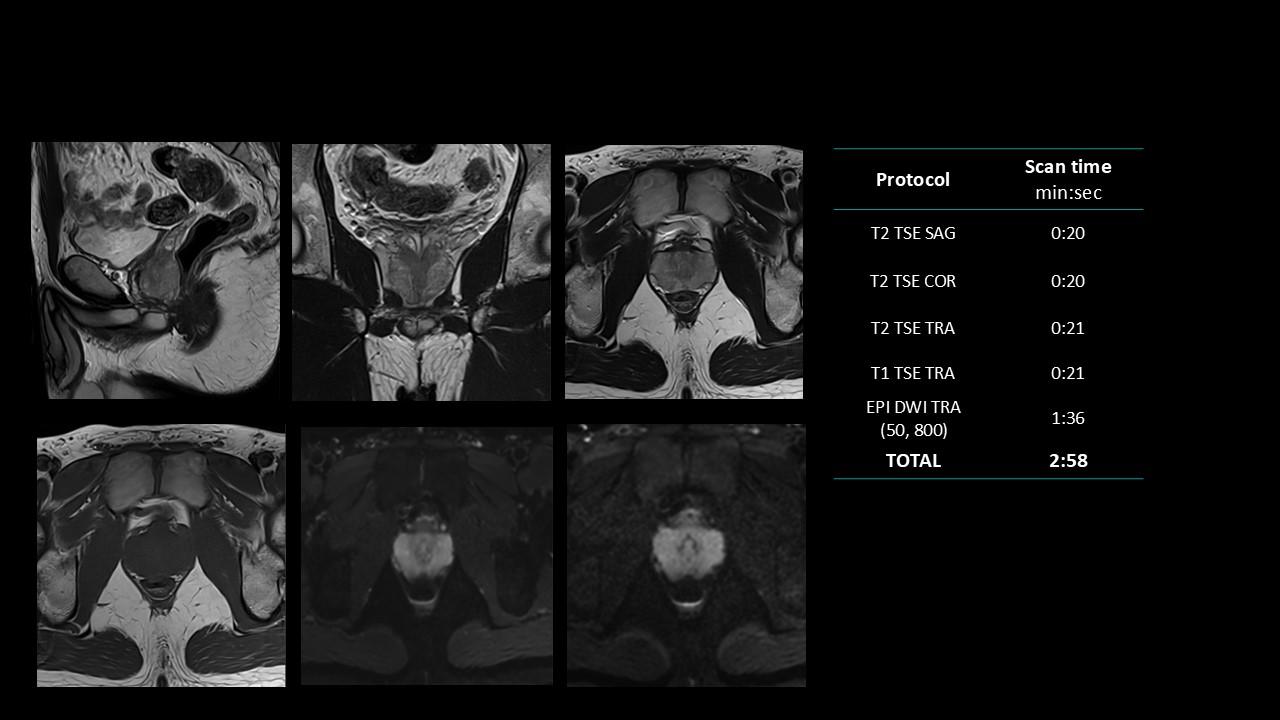

The Deep Resolve protocols are a set of advanced 3T MR imaging protocols designed to achieve high-quality diagnostic imaging with significantly reduced acquisition times.

Enabled by Deep Resolve, the AI-powered image reconstruction technology, these protocols deliver high-quality scans in approximately three minutes across a wide range of anatomical regions.

Developed and meticulously evaluated by Dr. Seong-ho Lee of Leaders Radiology Hospital in Seoul, Korea, the protocols integrate deep learning technology to enhance imaging efficiency while maintaining diagnostic detail.

By reducing scan duration, they improve workflow efficiency and patient experience without compromising image quality.